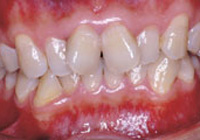

症例1:乱杭歯「歯並びが乱れている」

治療前